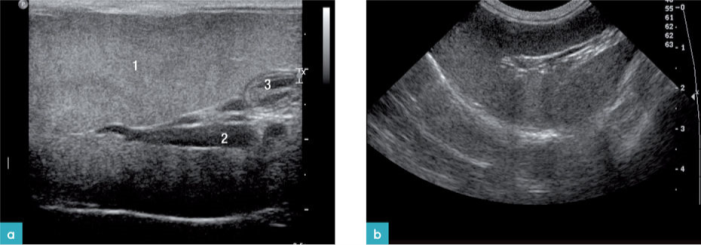

扫查脾脏通常采用仰卧位或右侧卧位。脾脏所处的位置非常浅表,建议使用高频探头扫查,正如扫描其他的腹腔脏器一样,需要将腹部上的毛发剔除,将腹壁上的毛发剔除,涂抹超声耦合剂,从脾脏的矢状面和横截面上全面地观察脾脏。

脾脏位于左侧上腹部,靠近胃底部、左肾头极与左侧腹壁(图1)。脾脏有两个表面:体壁面与脏器面。体壁面朝向左侧腹壁,表面凸起。脏器面(又称肠系膜面)朝向内侧,脾门在长轴上将脾脏分成两个部分(图2)。

猫的脾脏呈舌状,脾尾比脾体和脾头宽。脾脏的横截面呈三角形,显示脾脏尾部比脾脏的头部和中部都要宽,猫脾脏的相对体积较犬的小,且位置更为固定。大网膜上的胃脾韧带把脾头固定在胃底。猫的脾体和脾尾的游离性稍微大一些,但仍然不如犬脾脏的游离性大。

健康动物的脾脏边界清晰,被膜薄而光滑(图2和图3)。脾脏的脏器面的轮廓不规则,是因为在脾门的地方有血管进出。横断面上的脾脏呈三角形(图4)。二维超声图像上很难看到脾动脉进入脾脏,需要使用彩色多普勒才能识别脾动脉(图3)。